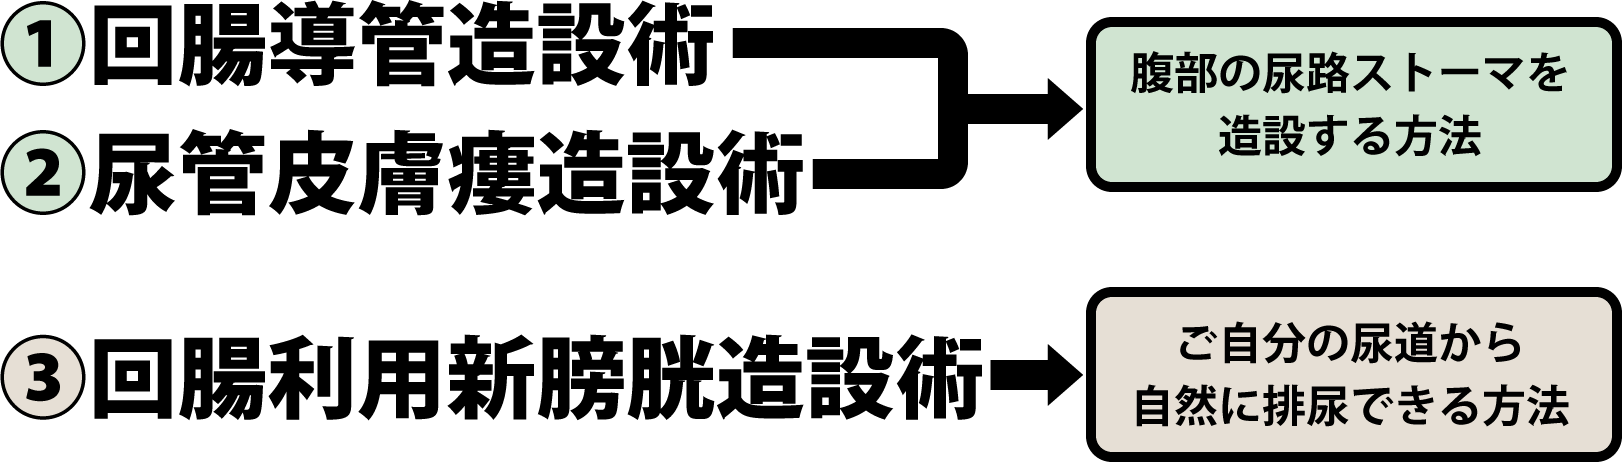

究める鏡視下膀胱全摘術・尿路変向術 Level up LRC, RARC | 三木。メジカルビュー社|泌尿器科|究める鏡視下膀胱全摘術・尿路変向。ロボット支援膀胱全摘除術(RARC) | 岩手医科大学 泌尿器科学講座。★3月精米★ 令和6年産 福井県産 いちほまれ 5kg 白米 精米。膀胱がん【泌尿器科疾患について】 - 東京慈恵会医科大学 泌尿器科。膀胱がん|KOMPAS。手術手技(膀胱全摘除術) | 領域情報 | アステラスメディカルネット。膀胱がん|KOMPAS。周術期の負担を軽減し早期社会復帰を!「ロボット支援腹腔鏡下。腎盂尿管移行部狭窄症に対するロボット支援腹腔鏡下腎盂形成術。朝倉書店『内科学』(第12版)デジタル付録。腹腔鏡下尿膜管摘出術及び左腎摘出術 - Olympus Professional。ロボット手術の定番!新品、未使用です。間違って2冊買ってしまったので、ページを開いてもいないため、本屋さんの「売上スリップ」も付いたままの全くの新品です。膀胱がんの外科治療について | 小野薬品 がん情報 一般向け。